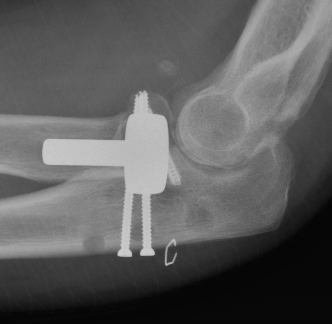

Terrible Triad

Definition

Elbow dislocation with radial head fracture + coronoid fracture + MCL tear

Technique

Surgical Algorithm

Principles

1. Restore coronoid stability - ORIF type II / III, suture repair type I

2. Restore radial head stability - radial head ORIF or arthroplasty

3. Restore lateral stability - LCL repair and common extensor origin +/- reconstruct +/- internal brace

4. +/- Restore medial stability - repair MCL if residual stability

5. +/- External fixation / internal joint fixation

| Type II / Reconstructable radial head | Type III / Radial head arthroplasty |

|---|---|

|

Lateral / Kocher approach - ORIF radial head with screws/ plate - LCL +/- common extensor origin repair - reassess stability |

Lateral / Kocher / Kaplan / EDC split approach - excise radial head - can suture small coronoid process fracture through gap - radial head replacement - LCL +/- common extensor origin repair - reassess stability

|

|

Unstable - medial approach - FCU split / over the top approach to coronoid process - ORIF coronoid process with sutures / buttress plate / screws - MCL repair +/- common flexor origin repair - reassess stability |

Unstable - medial approach - FCU split / over the top approach to coronoid process - ORIF coronoid process with sutures / buttress plate / screws - MCL repair +/- common flexor origin repair - reassess stability |

| Unstable - external fixation | Unstable - external fixation |

Radial head replacement with lag screw fixation of Type II coronoid

Radial head replacement with lasso fixation of small coronoid fragment

Results

Outcomes

- systematic review of terrible triad injuries

- mean flexion arc 110 degrees

- 30% complication

- 8% revision

- 11% HO

- 3% ulnar nerve